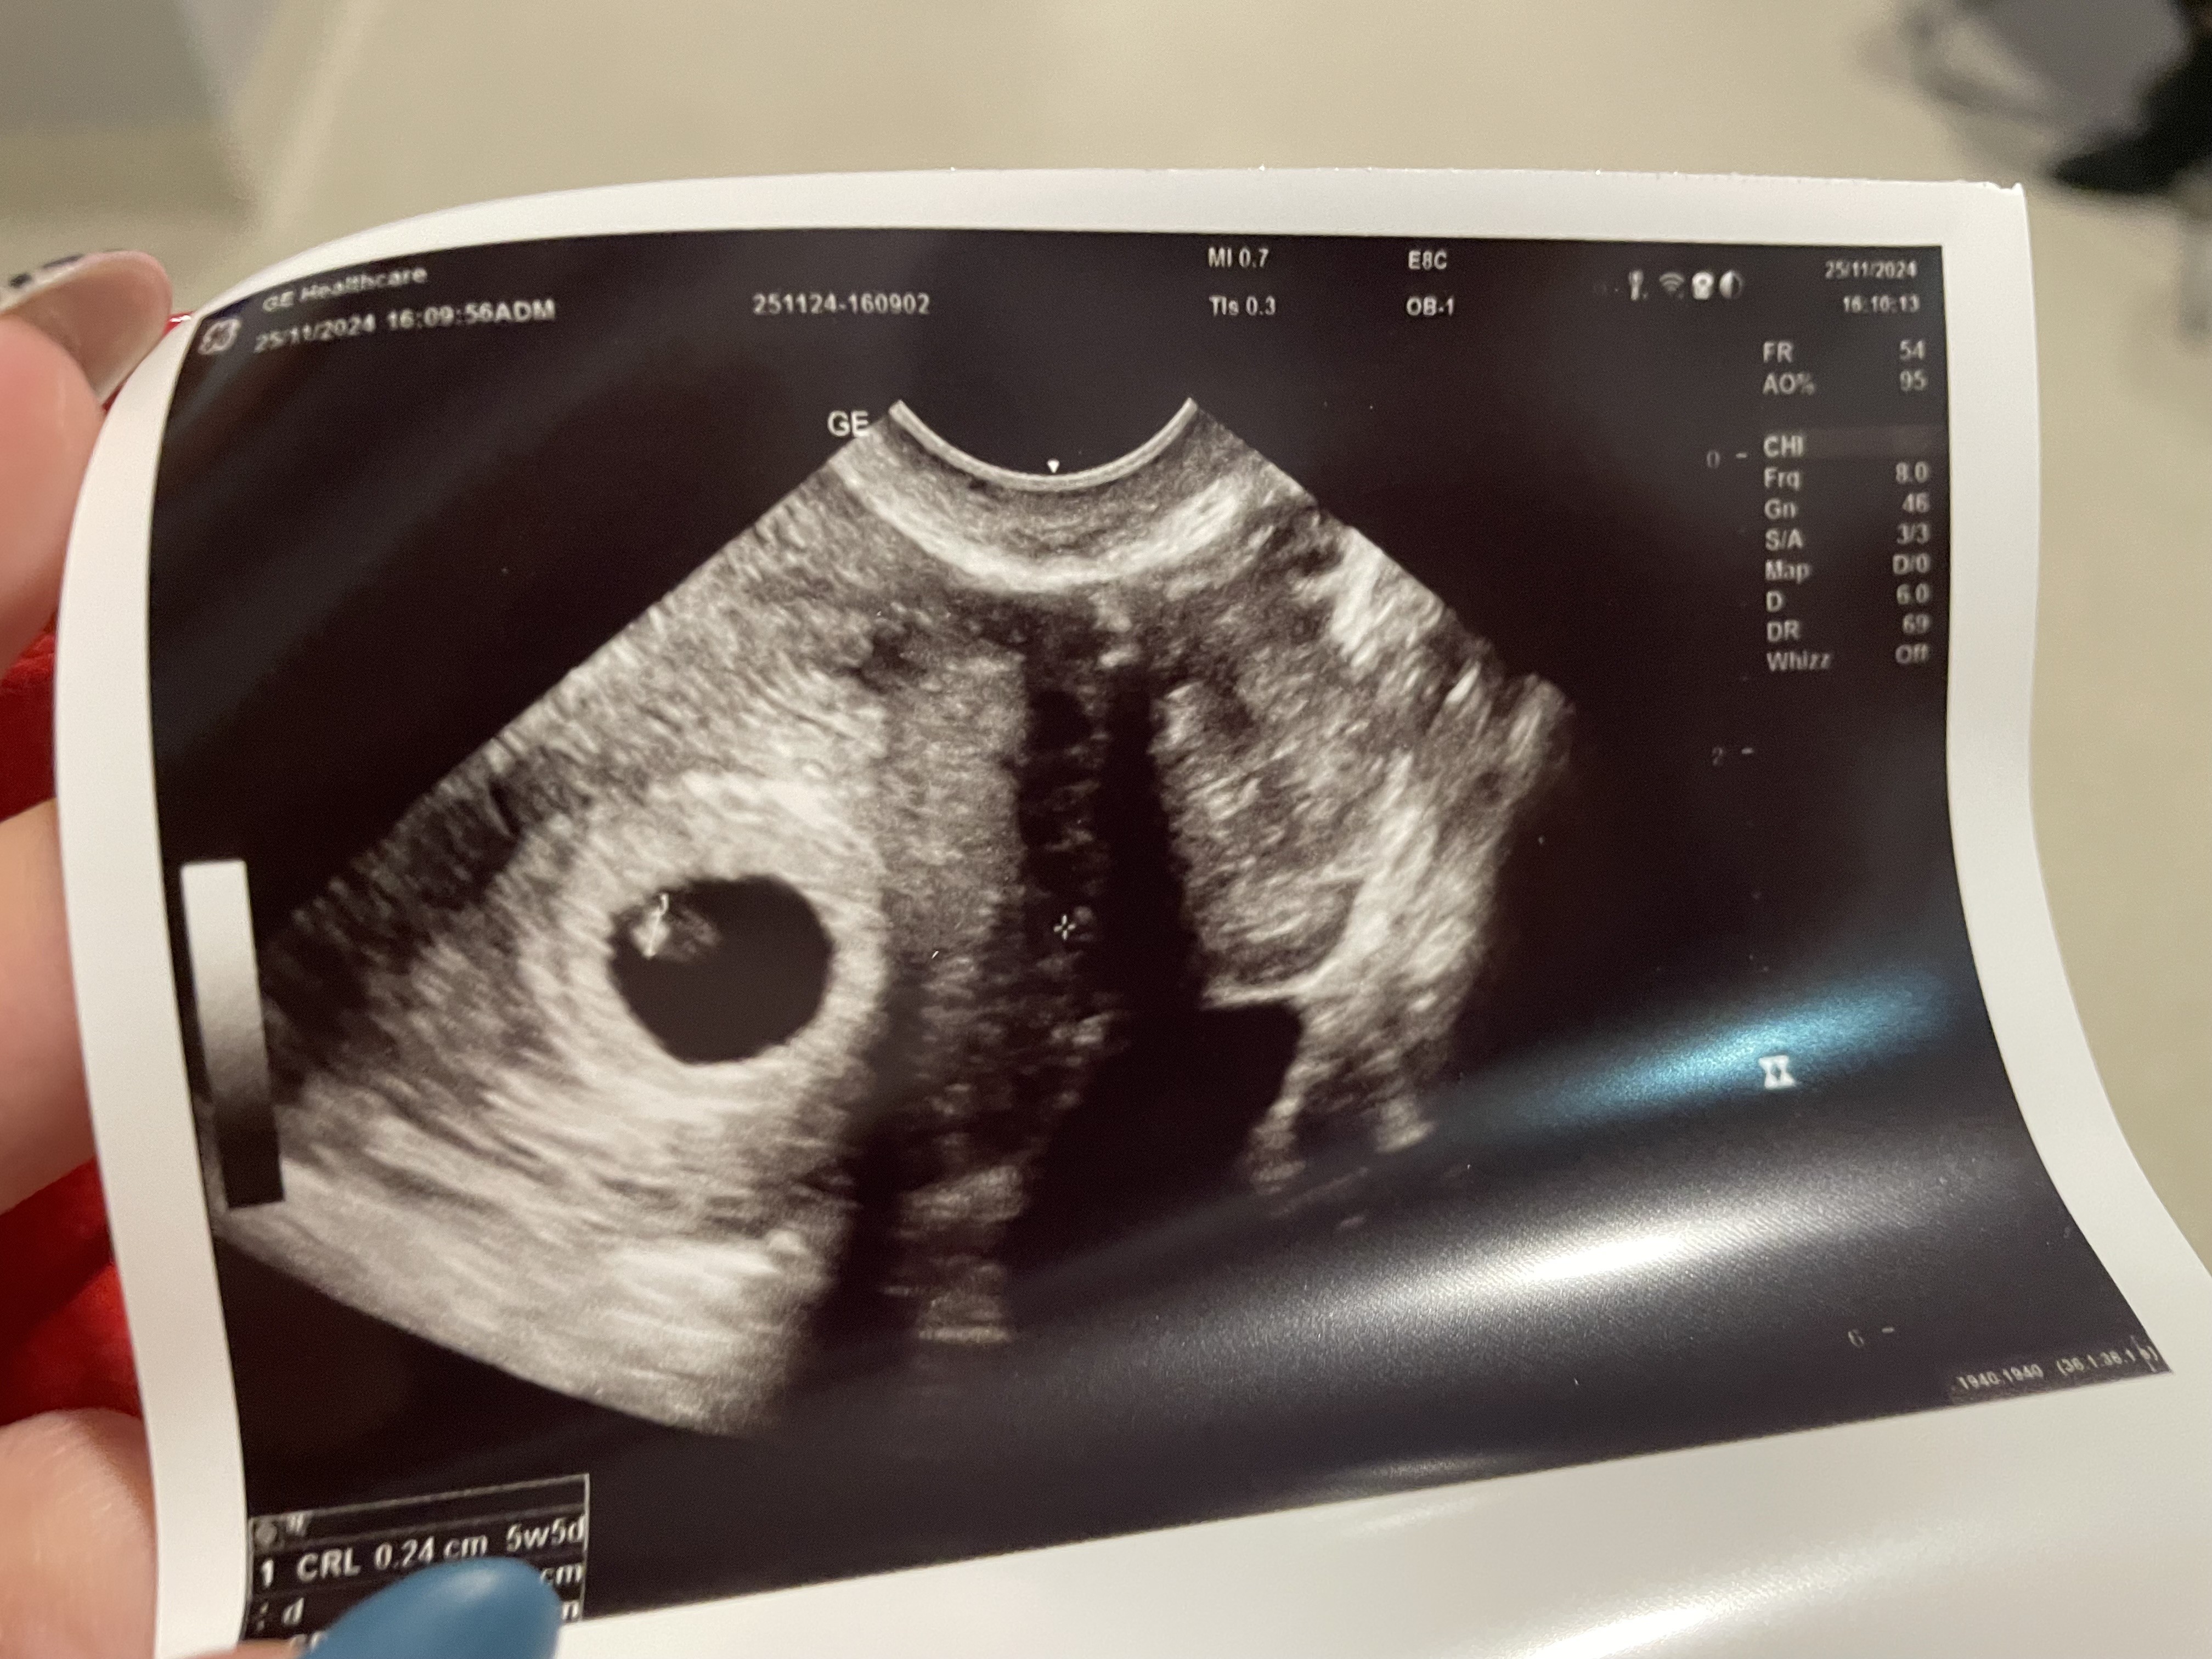

• IMG_7598.jpeg

IMG_7598.jpeg

2,2 MB · Wyświetleń: 124